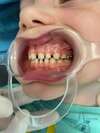

Intrabuccale face - Avant traitement 1 (04-03-2024) - 1